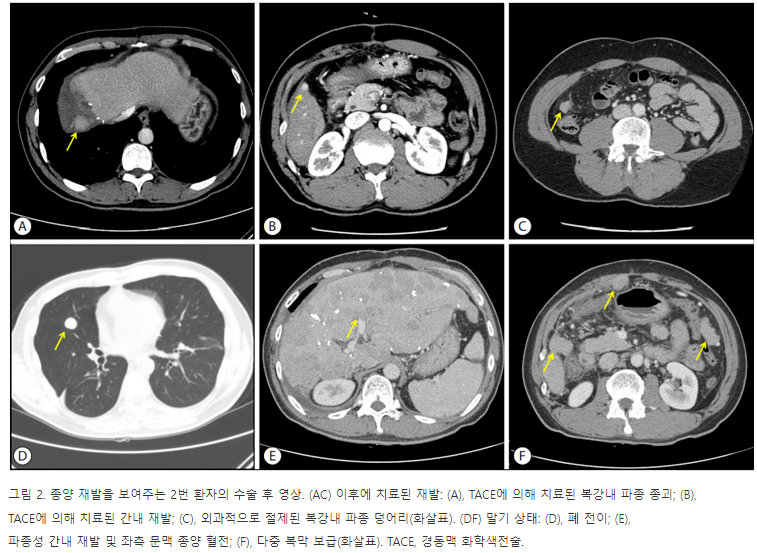

수술 전 TACE를 시행한 4명의 환자에서 수술은 TACE 후 짧게는 7일, 길게는 41일 후에 시행되었으며, 수술 후 환자들의 중앙 추적관찰 기간은 28.3(24.3-62.3)개월이었다. 환자들 모두에게 해부학적 간절제술이 시행되었다(Table 2). 추적관찰 기간 중 2명(40%)의 환자에서 재발이 있었으며, 재발 시기는 수술 후 1.9개월, 40.0개월이었다. 수술 후 1.9개월만에 재발을 한 2번 환자의 경우 처음 종양이 있던 부위에 인접한 횡경막에서 종양파종에 의한 것으로 보이는 재발이 처음 발생하였고, 이후 간 내 재발이 추가적으로 발생하였다. 이 병변들에 대해서는 TACE로 반복 치료하였고, 수술 후 13개월째 발생한 우하복부 복강 내 재발에 대해서는 수술적 절제를 시행하였다. 그럼에도 불구하고 간세포암이 간전체에 퍼지고, 다발성 폐전이, 문맥 종양 혈전, 복강 내 파종이 진행하여 수술 후 24개월 만에 결국 사망하였다(Fig. 2). 1번 환자는 수술 후 40.0개월 만에 처음 재발 병소가 발견되었다. 이전 수술부위와는 떨어진 6분절에 1 cm 크기의 간 내 재발이었고, 고주파 열치료로 치료하였다. 이후 13개월 뒤 다시 4분절에 또 다른 간 내 재발이 발생하여, TACE가 시행되었다. 두 차례의 재발 치료 후 8개월 동안 추가적인 병변발생 없이 추적관찰 중이다. 최종적으로 간절제술이 시행된 파열 간세포암 환자 5명 중 2명의 환자(40%)에서 추적관찰 중 재발이 발생하였고, 간세포암 파열에 의한 복강 내 파종은 한 명(20%)에서만 발생하였다. 그리고 복강 내 파종이 있었던 한 명(20%)만이 추적관찰 중 사망하였다.